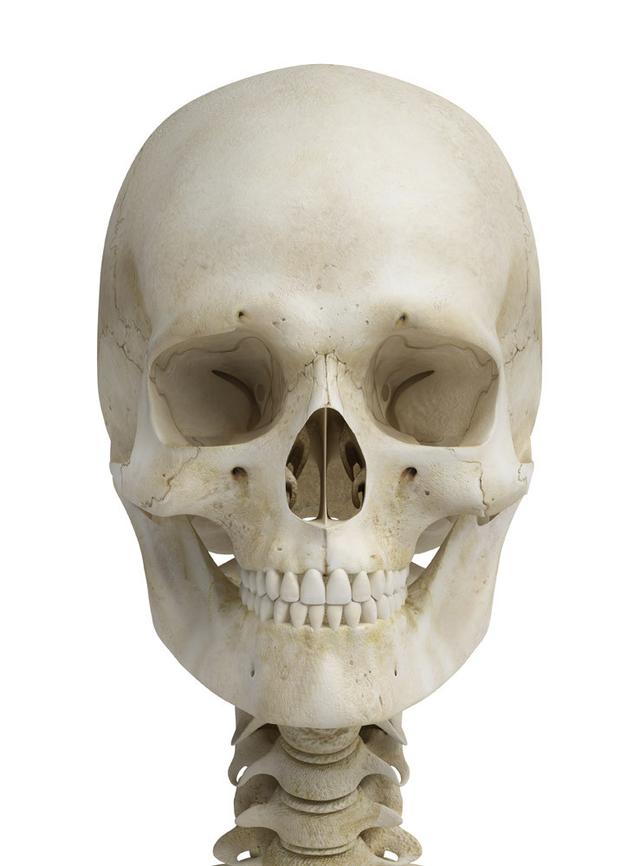

从一方面来说,人类是弱小的,容易生病,容易受伤,但从另一方面来说,人类也是强大的...